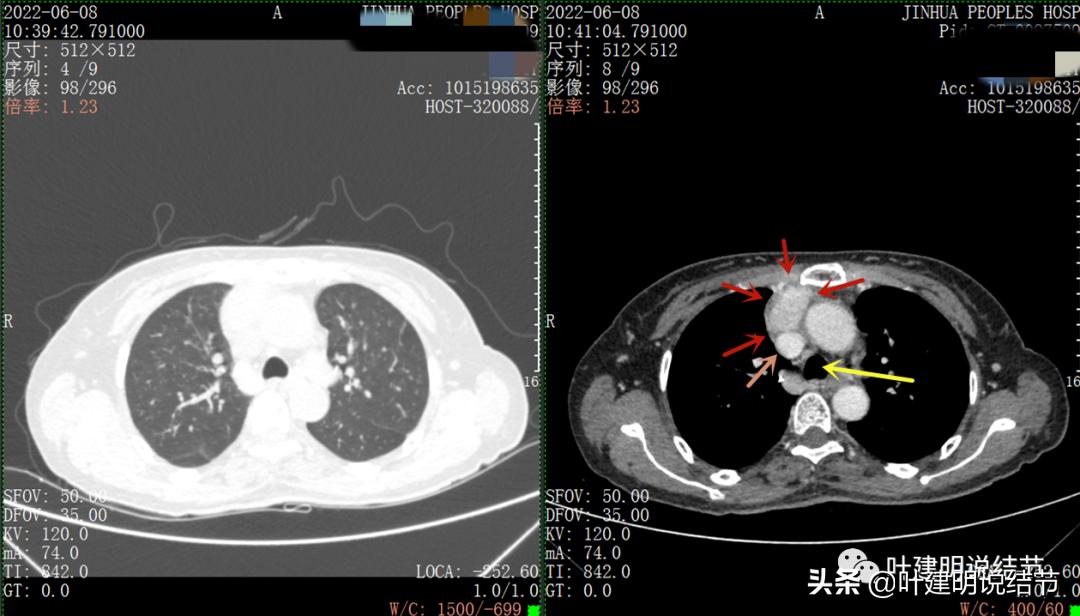

以下图片左侧是肺窗,右侧是纵隔窗。红色箭头示病灶,桔色箭头示无名静脉,黄色箭头示支气管,砖色箭头示上腔静脉,蓝色箭头示主动脉,紫色箭头示肺动脉。

病灶占据前纵隔从上到下全程,多中心,密度不均,对心脏与大血管有压迫,没有明显侵犯

病灶表面不平,中间有坏死

特别显示与无名静脉的关系